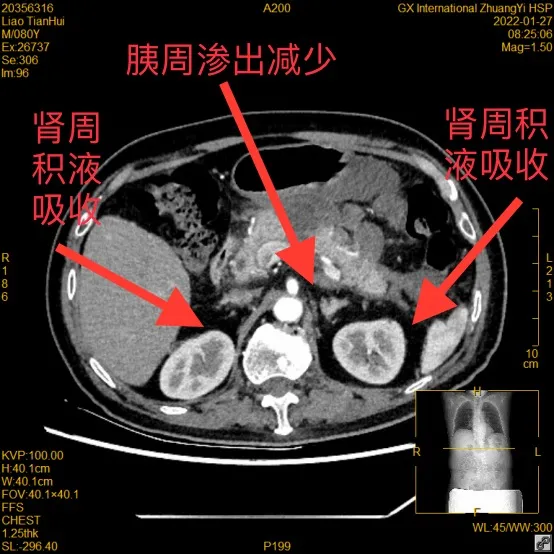

最新的CT检查显示,廖爷爷的胰腺渗出减少,双侧肾周积液已被身体吸收,病情稳定